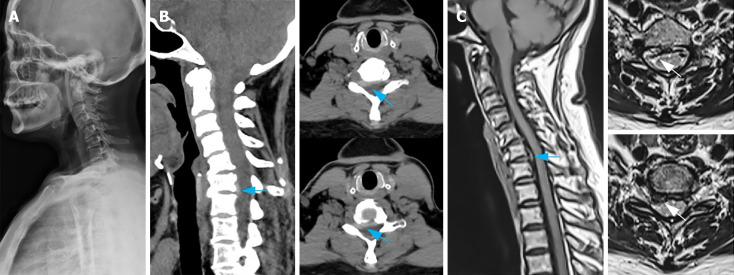

We here present a 57-year-old woman diagnosed as having cervical spondylotic radiculopathy (CSR) who was scheduled for anterior cervical decompression and fusion. During post-anesthetic positioning, a sudden hypertensive surge was observed when the patient was in a supine position with the neck being slightly extended. This surge was promptly reversed through cervical flexion and head elevation. This event however required an alternate surgical approach for recovery-posterior laminoplasty and endoscopy-assisted nucleus pulposus removal. Following the 6-month outpatient follow-up period, cervical flexion and extension activities substantially improved in the patient without any episodes of increase in acute blood pressure.

我们在此介绍一名57岁女性,被诊断为神经根型颈椎病(CSR),计划接受颈椎前路减压融合术。在麻醉后体位摆放过程中,当患者处于颈部稍伸展的仰卧位时,突然出现高血压激增。通过颈椎屈曲和抬头,这种激增迅速得到逆转。然而,这一事件需要采用另一种手术方法进行恢复——后路椎板成形术和内镜辅助下髓核摘除术。经过6个月的门诊随访期,患者的颈椎屈伸活动有了显著改善,且未出现急性血压升高的情况。